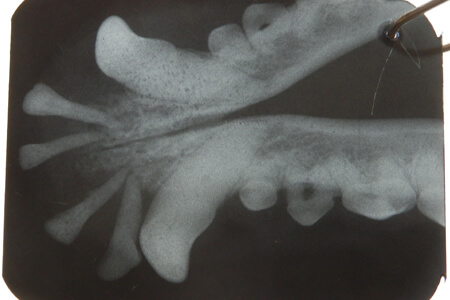

Специалисты нашей клиники успешно лечат болезни ротовой полости, это снятие зубных камней при помощи ультразвукового прибора с последующей полировкой эмали, без боли удаляют безнадежно больные зубы, молочные зубы, запломбируют больной зуб, исправят прикус и др. Стоматолог проводит обучающие занятия с владельцем животного о мерах профилактики болезней зубов.